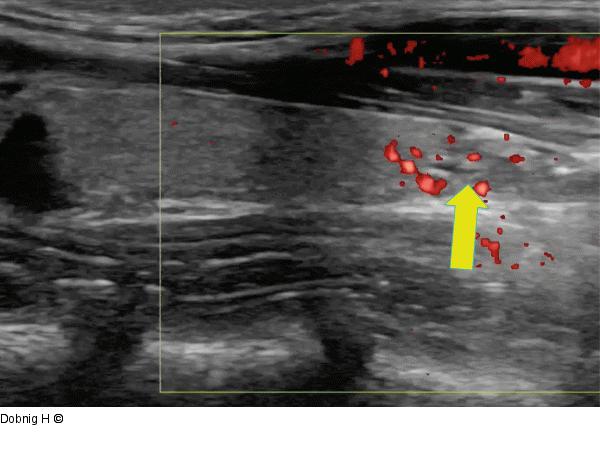

Abbildung 9: Alkoholablation - Schilddrüse Längsschnitt durch die Schilddrüse nach der Ablation. Im kaudalen Drittel (Pfeil) zeigt sich ein vollständig kollabierter Zystenbalg. |

Längsschnitt durch die Schilddrüse nach der Ablation. Im kaudalen Drittel (Pfeil) zeigt sich ein vollständig kollabierter Zystenbalg. |